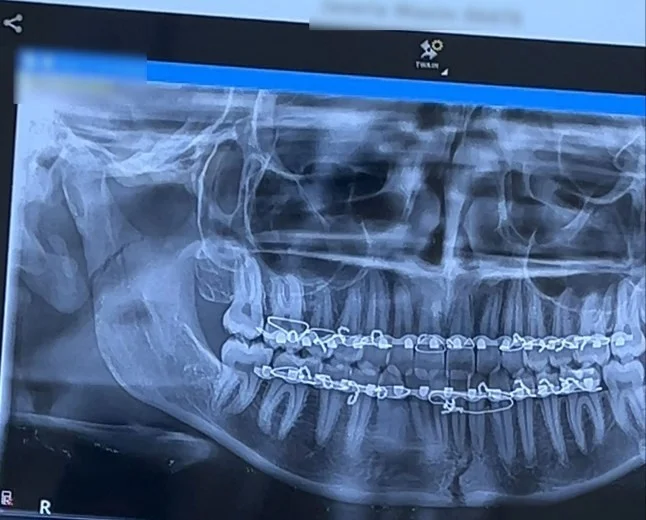

At the hospital, X-rays and CT scans showed that the girl had two jaw fractures.

After an hour-long procedure, the jaw was put back in place, and plates were installed on the upper and lower gums, fixed with wire for six weeks.